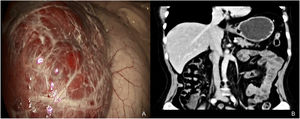

A liver hemangioma measuring 14 × 11 × 10 cm was found during the surgery that completely involved segments II and III (Fig. 2A).

During the postoperative outpatient follow-up, the patient was asymptomatic, with improved quality of life. At postoperative year one, the patient has had no symptoms and the control tomography scan showed no tumor recurrence (Fig. 2B).